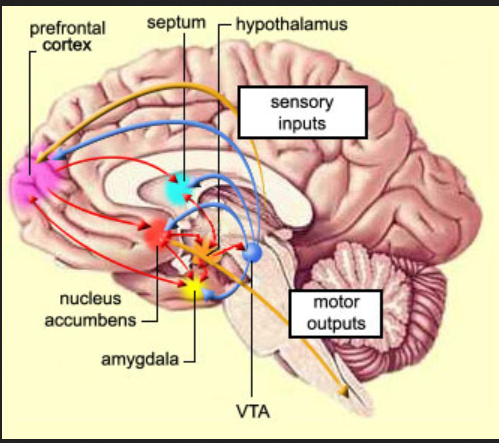

58 brain Septum attacks on Sept 11,2001

Septum pellucidum – Wikipedia

The septum pellucidum (translucent hedge) is a thin, triangular, vertical double membrane separating the anterior horns of the left and right lateral ventricles of …

Know your brain: Septum — Neuroscientifically Challenged

Dec 8, 2016 – The term septum, when used in reference to the brain (it is a common anatomical term used to refer to a partition), indicates a subcortical …

Know your brain: Septum

Know your brain: Septum

Know your brain: Septum ordered attack for September 11, 2001